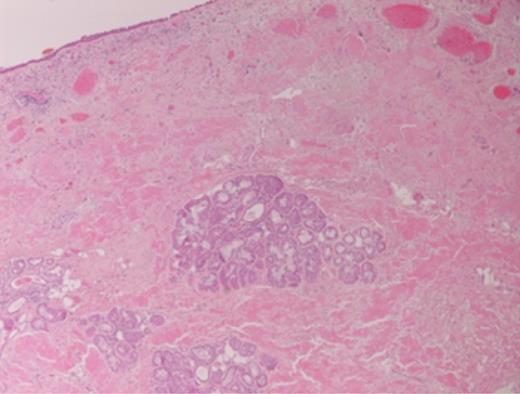

Histopathology revealed prominent acellular, eosinophilic deposits within the stroma (Figs 1 and 2). Under polarized light, Congo red staining showed the characteristic apple-green birefringence of amyloidosis. No dysplasia or malignancy was seen.

Congo red staining of the biopsy sample. Histology shows an acellular, amorphous, eosinophilic material deposit in the stroma, with perivascular and periglandular accentuation. Typing of the specimen is based on clinical and laboratory findings (including paraproteinaemia looking for an underlying myeloma, TTR gene rearrangement studies looking for the genetic defect in familial amyloid.)